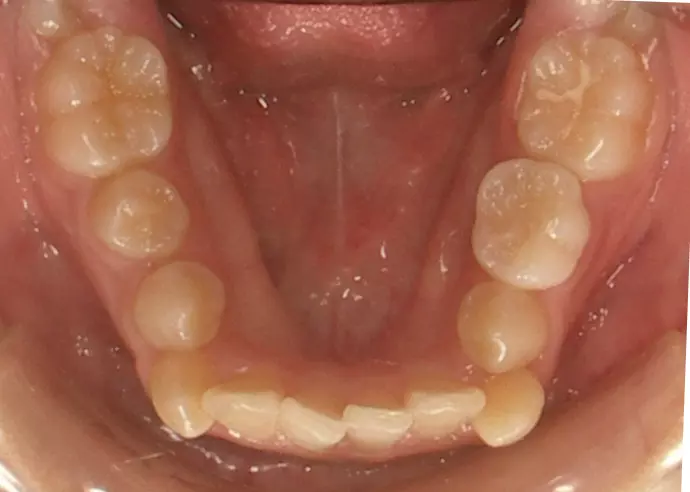

治療前